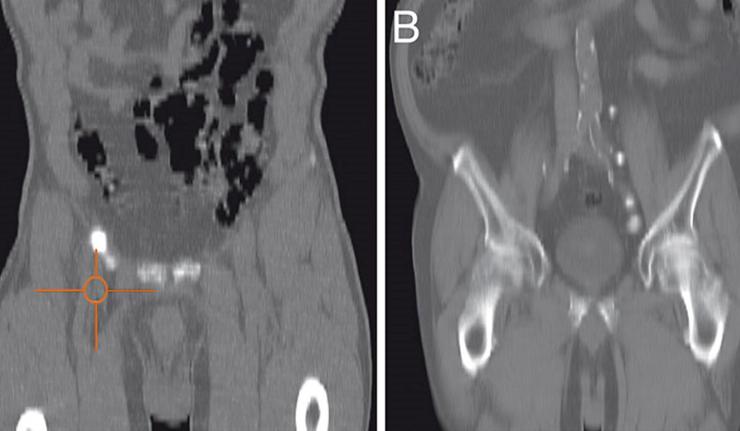

Βουβωνική λεμφαδενεκτομή

Η διαχείριση της λεμφαδενικής μεταστατικής οδού είναι κρίσιμης σημασίας για την επιβίωση των ασθενών με καρκίνο του πέους. Ο πρώτος σταθμός μετάστασης είναι πάντοτε οι βουβωνικοί λεμφαδένες και αυτό είναι το σημείο όπου η νόσος πρέπει να εντοπιστεί και να περιοριστεί. Η βουβωνική λεμφαδενεκτομή έχει διαγνωστικό και θεραπευτικό ρόλο στον καρκίνο του πέους.